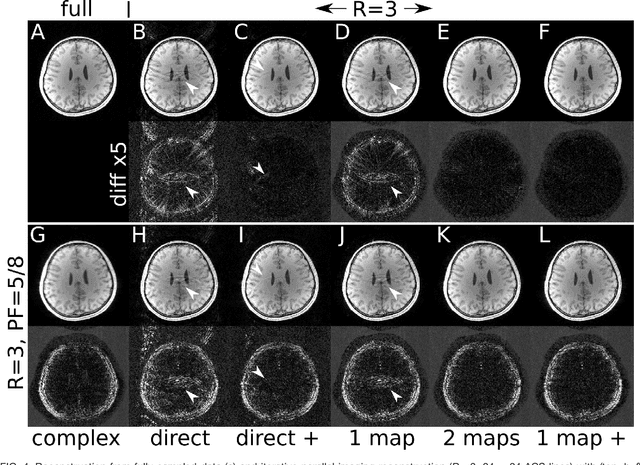

Purpose: To develop an ESPIRiT-based method to estimate coil sensitivities with image phase as a building block for efficient and robust image reconstruction with phase constraints. Theory and Methods: ESPIRiT is a new framework for calibration of the coil sensitivities and reconstruction in parallel Magnetic Resonance Imaging (MRI). Applying ESPIRiT to a combined set of physical and virtual conjugate coils (VCC-ESPIRiT) implicitly exploits conjugate symmetry in k-space similar to VCC-GRAPPA. Based on this method, a new post-processing step is proposed for the explicit computation of coil sensitivities that include the absolute phase of the image. The accuracy of the computed maps is directly validated using a test based on projection onto fully sampled coil images and also indirectly in phase-constrained parallel-imaging reconstructions. Results: The proposed method can estimate accurate sensitivities which include low-resolution image phase. In case of high-frequency phase variations VCC-ESPIRiT yields an additional set of maps that indicates the existence of a high-frequency phase component. Taking this additional set of maps into account can improve the robustness of phase-constrained parallel imaging. Conclusion: The extended VCC-ESPIRiT is a useful tool for phase-constrained imaging.